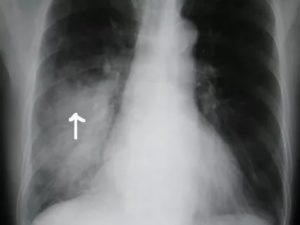

Рентген симптомы болезни четко визуализируются при разгаре заболевания. Темные пятна на снимке обусловлены снижением воздушности легочной ткани.

Вначале заболевания инфильтраты прослеживаются, как «дымка». Такая тень имеет гомогенную структуру, среднюю интенсивность. Она быстро превращается в классический пневмонический очаг.

Чтобы определить очаговую пневмонию на снимке, предлагаем читателям ее признаки:

- Наличие интенсивного инфильтрата негомогенной структуры;

- «Плохая» тень имеет нечеткий контур;

- При воспалении плевры наблюдается линейная тяжистость или уровень жидкости в реберно-диафрагмальном синусе на стороне поражения;

- На фоне разрешения процесса участок инфильтрации становится сильно неоднородным за счет участков распада и заживления легких.

Крупозная пневмония на рентгенограмме прослеживается, как крупное среднеинтенсивное затемнение. Оно проецируется на одну или обе легочные доли. Болезнь провоцируется палочкой Фриндлера и относится к ряду тяжелых жизне угрожающих заболеваний.